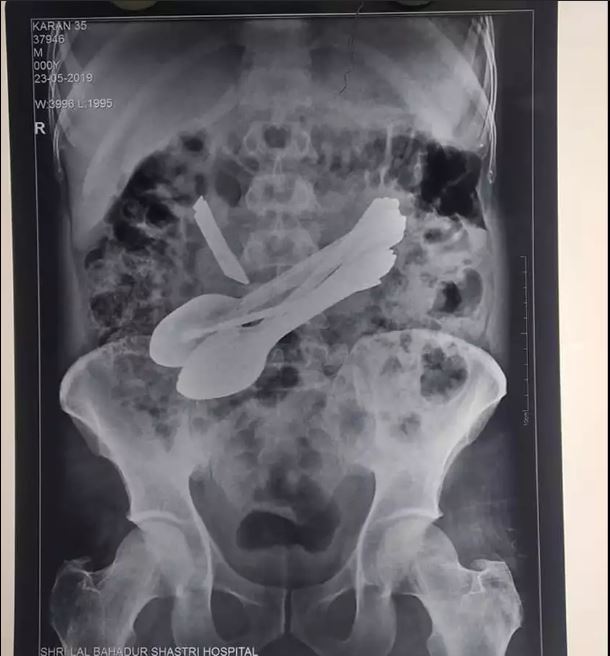

According to a report by The Times Of India, the doctors took an X-ray and were shocked to discover seven spoons, a knife, two toothbrushes, two screwdrivers and even a small rod in his gut.

According to the news portal, the 35-year-old man was reportedly rushed to the medical center by his family after complaining of severe pain. Doctors were stunned to find the tip of a knife protuding out from his stomach.